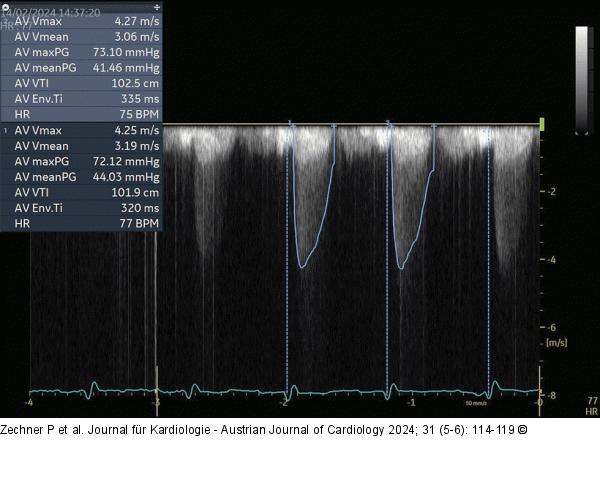

Abbildung 6: Echo AS mit KM: gutes CW-Spektrum; gleicher Patient wie Abb. 5. |

Abbildung 6: Echo

AS mit KM: gutes CW-Spektrum; gleicher Patient wie Abb. 5. |